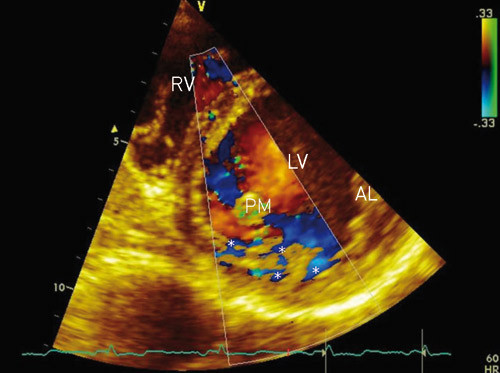

During embryogenesis, the mesh of muscle fibres making up the heart normally becomes compacted while the intertrabecular sinusoids degenerate. This compaction process occurs in gestational weeks 5 – 8, and results in transformation of intertrabecular sinusoids to capillaries. It starts in the epicardium and progresses inward towards the endocardium, from the base of the heart to apex, and is more complete in the left ventricle (LV) than in the right ventricle (RV). Development of the coronary circulation occurs in the same period (1, 13) and is inhibited in the presence of noncompaction. The result is multiple persistent and prominent ventricular trabeculae, and deep intertrabecular recesses which communicate with the ventricular cavity and not with the coronary circulation (fig 1, fig 2). The ventricular cavity and the intertrabecular recesses are covered by a continuous endothelium (1, 2, 5). Predilection sites for noncompaction (normal findings in fish, amphibian and reptile hearts [4]) are the mid and distal segments of the lateral and inferior walls, as well as in the apical region (5, 9, 13). The extent of changes varies among patients (1, 4).

Deep intertrabecular recesses that communicate with the ventricular cavity.

The patients are prone to thromboembolic events (due to thrombus formation in the deep intertrabecular recesses) and supraventricular tachyarrhythmias (2, 3, 8, 9). Prophylactic anticoagulation treatment should therefore be used quite liberally (1, 9, 16).